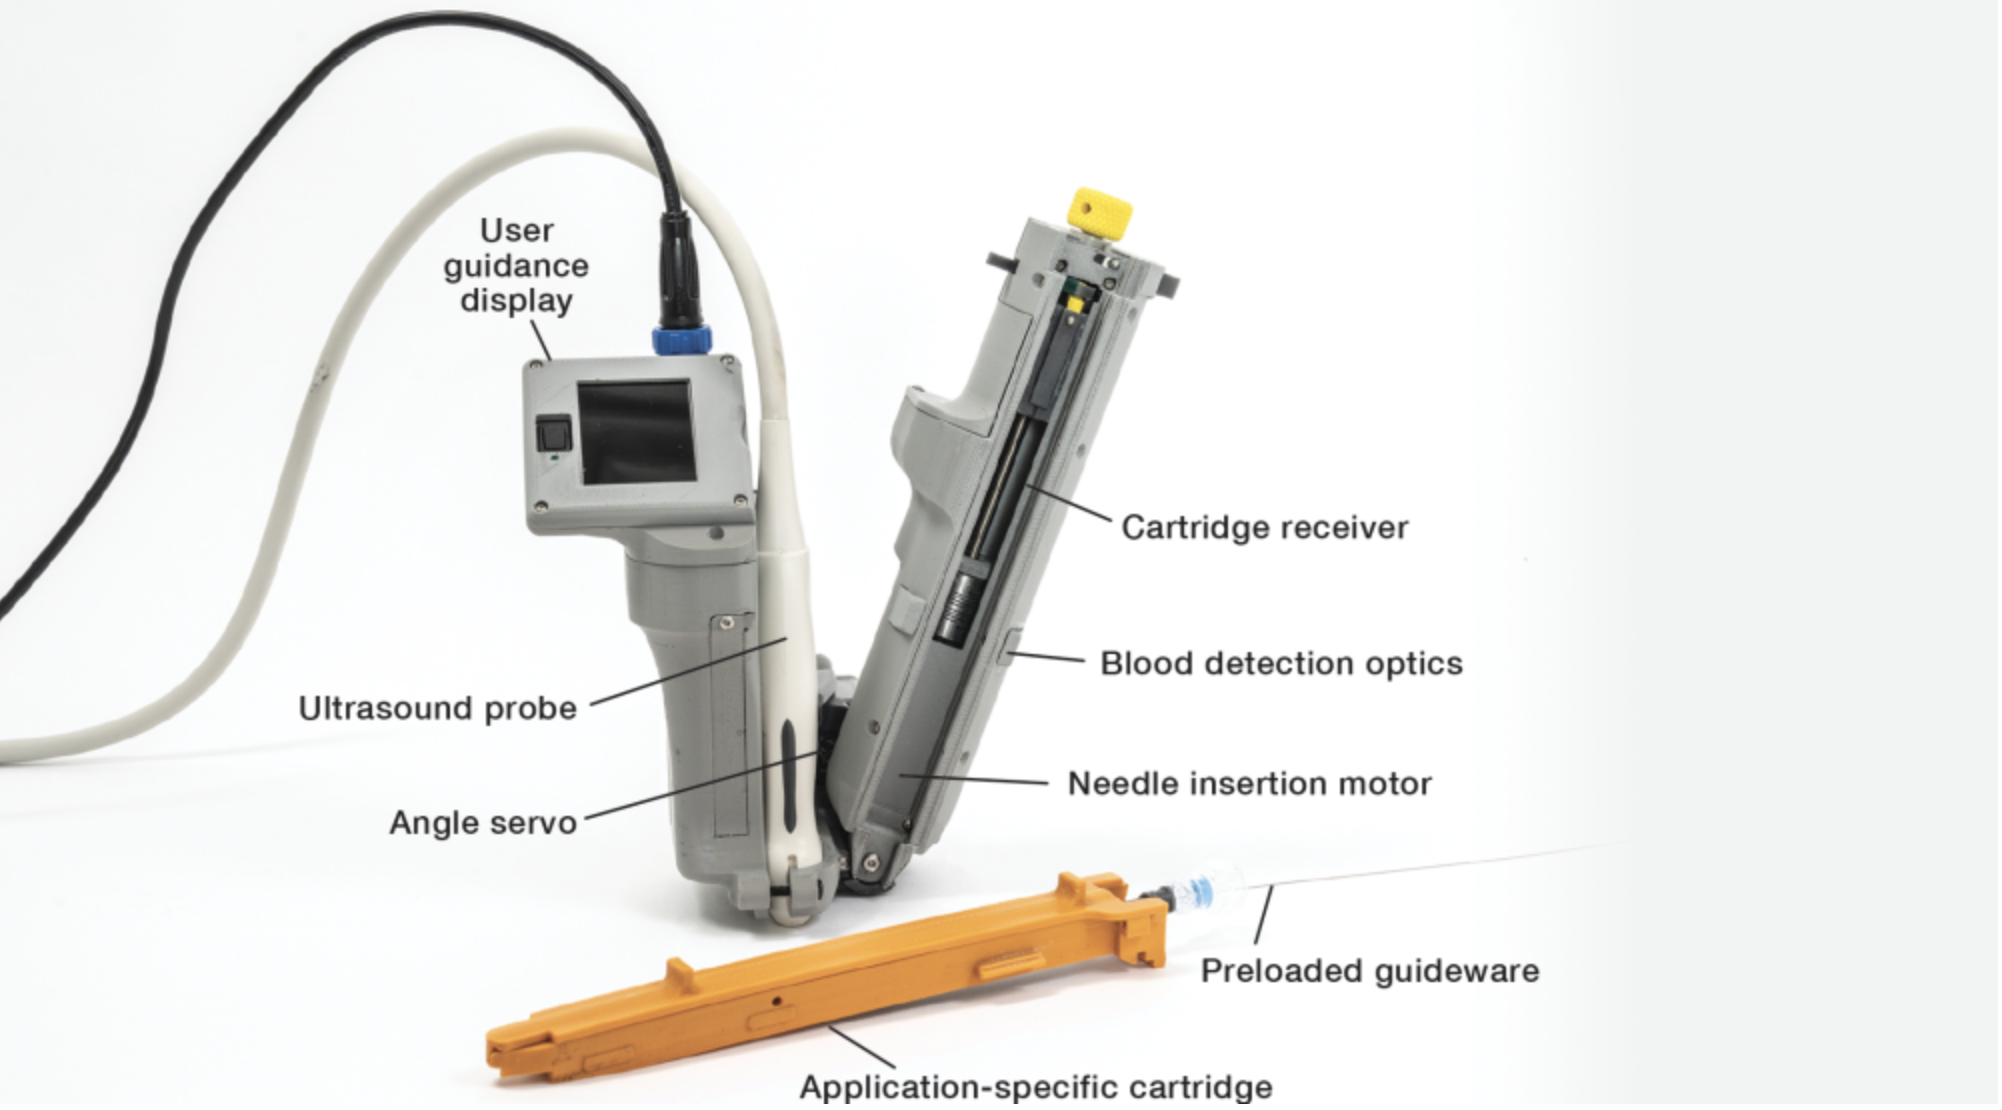

MIT LL - AI Guided Ultrasound Intervention Device